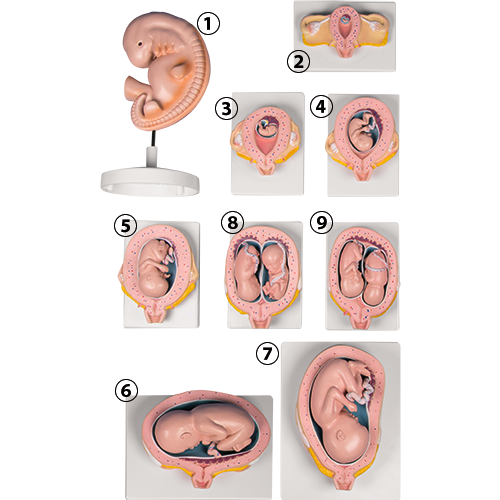

子宮内胎児の発育過程を示す L11 妊娠模型デラックスシリーズ。

Amazon.co.jp : 胎児成長過程モデル 胎児モデル 胎児子宮胚発育モデル 医療教材 解剖学教材 : ホーム&キッチン。

Amazon.co.jp: 胚発生モデル 胎児の成長過程表示モデル 受精卵 ポピュラーサイエンスデモ用生物学教育モデル : 産業・研究開発用品。

Amazon.co.jp: 胎児発育モデル - 10ヶ月の胎児妊娠モデル - 胎児の成長および発達プロセスモデル 科学教育用の胚発育モデル :産業・研究開発用品。

子宮内胎児の発育過程を示す L11 妊娠模型デラックスシリーズ。